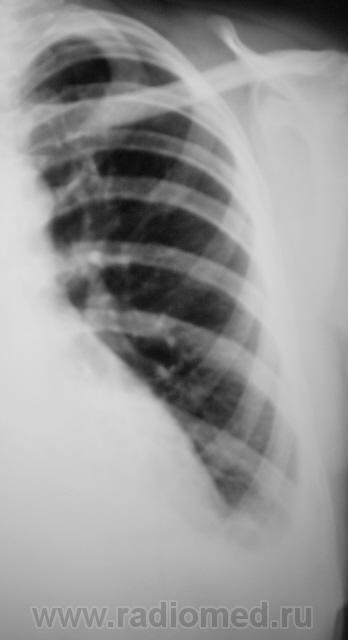

Пациент направлен на рентгенографию ОГК с диагнозом "пневмония".

на плевральный выпот в левом заднем синусе.

да, похоже на левосторонний экссудативный плеврит. Причина?